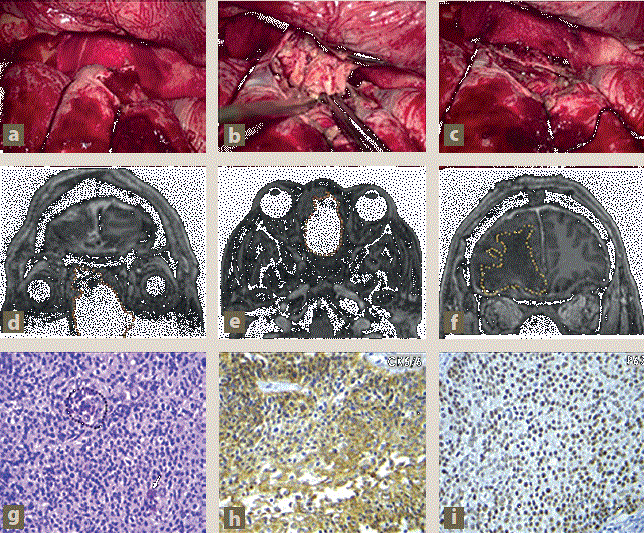

Imagen: Prado Hernández et al.

Figura 5 Tumor nasal con extensión intracraneal. Fotografías transoperatorias. a) Apertura de la duramadre en el lóbulo frontal. b) Exéresis de tumor intradural junto a la duramadre. c) Bordes de tejido cerebral sin evidencia de lesión tumoral. Control postquirúrgico por imagen (resonancia magnética [RM] en T1 + Gd en cortes coronal, axial y coronal respectivamente), mostrando: ausencia de la lesión tumoral en las fosas nasales (puntos naranjas continuos), ausencia de la lesión tumoral en la región frontal derecha aunado a edema vasogénico adyacente (puntos amarillos continuos). Imágenes histopatológicas: g) Varias capas de células epiteliales con pleomorfismo nuclear, mitosis (puntos negros) e infiltrado linfocitario (flecha). h) Inmunohistoquímica CK5/6 que confirma el origen epitelial. i) Inmunohistoquímica P63 que confirma el origen epidermoide.